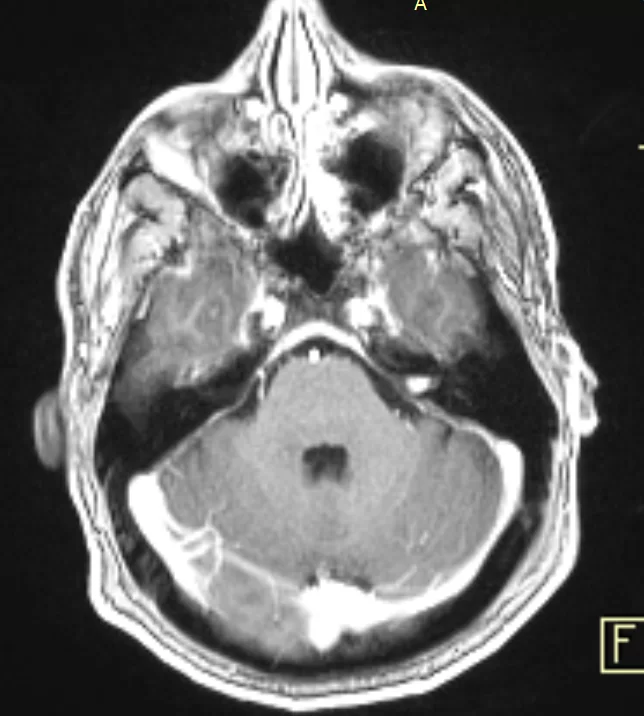

Ασθενής άνδρας, 39 ετών ο οποίος παρουσίασε έκπτωση ακοής αριστερά, διαγνώστηκε με μικρή ενδοκαναλική (δηλ. εντός του έσω ακουστικού πόρου) εξεργασία σύστοιχα, συμβατή με μικρό ακουστικό νευρίνωμα (αιθουσαίο σβάννωμα). Ο επανέλεγχος με μαγνητική τομογραφία λιθοειδών ανέδειξε μικρή (1χιλ) αύξηση του μεγέθους του νευρινώματος. Αναφερόμενος άτυπος σπασμός ημιπροσώπου αριστερά.